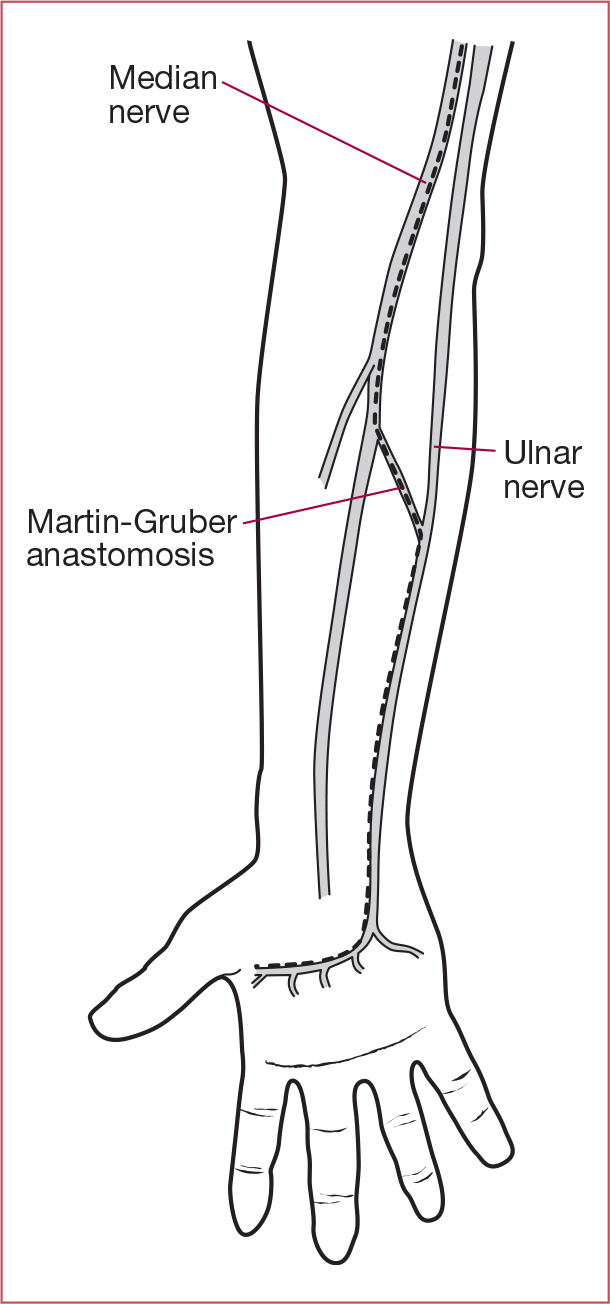

What are three NCS findings that could indicate a Martin-Gruber anastomosis?

- decreased distal amplitude of median nerve CMAP compared to proximal

- initial positive deflection of median nerve CMAP

- artifically fast CV